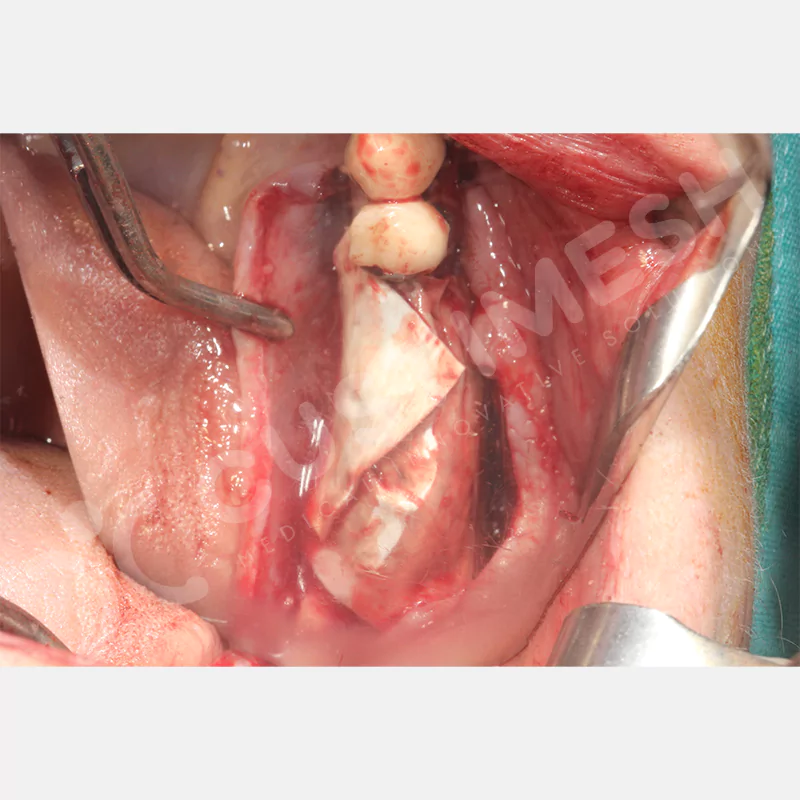

VAKA 1